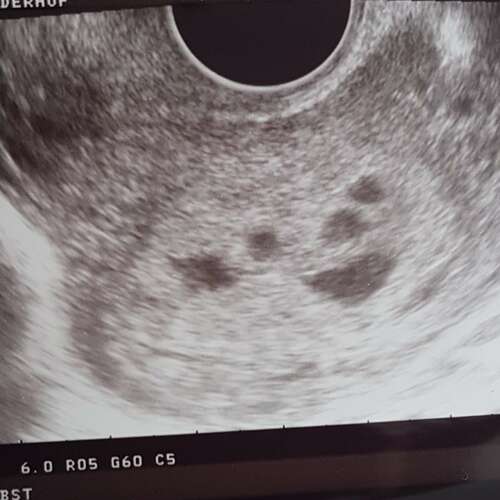

Dit is was de echo van mijn (nu nog) jongste. Inmiddels al wel 5 jaar terug ...

Dit was bij mij met 6 weken , ik had vorig jaar zelfde beeld als jou en dat is helaas niet goed afgelopen. Maar het kan nog alle kanten op. Had je al wel hartslag?